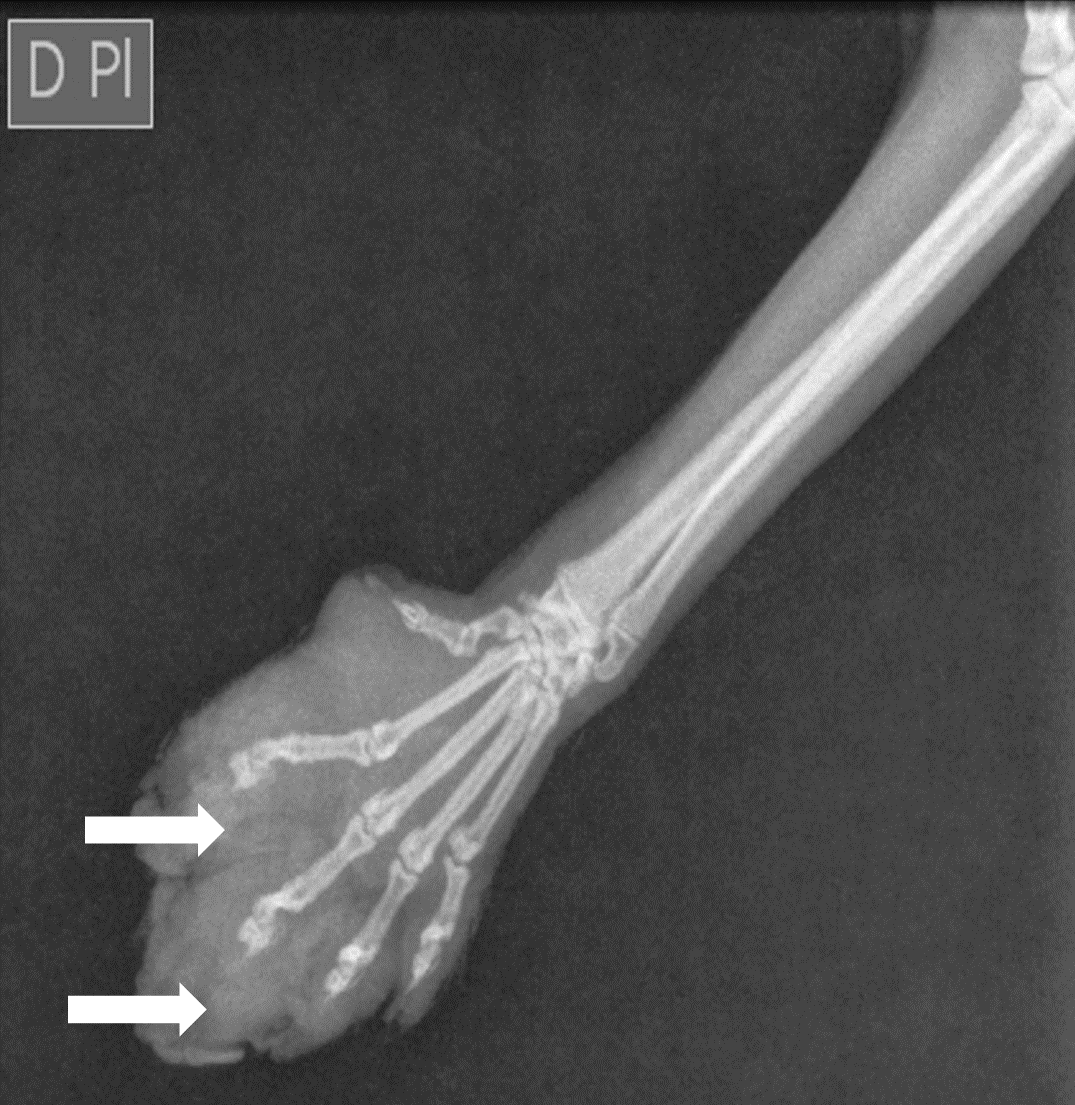

Radiography of the region, including the carpal joint and phalanges, showed only an increase in the volume of the soft tissue, suggesting an inflammatory process, with no observed bone abnormalities showed in the figure 2, the dorsopalmar projection radiography of the carpal, metacarpal, and phalangeal region.

Figure 2. Radiography in the dorsopalmar projection of the carpal, metacarpal, and phalangeal region reveals a pronounced increase in soft tissue volume adjacent to the metacarpal and phalangeal regions (arrows), with no evidence of radiographic changes in the bone structures.